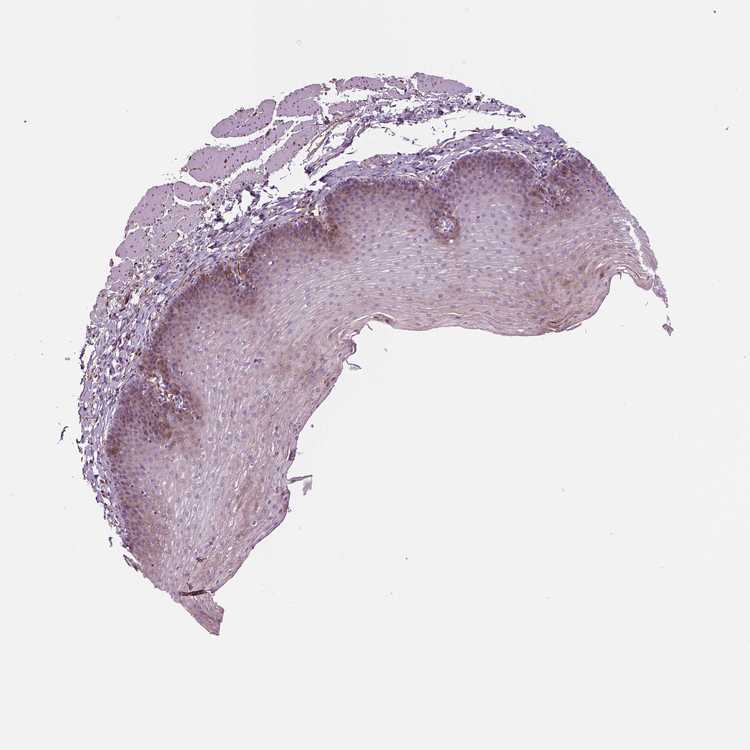

ESOPHAGUS - Antibody stainingi

Antibody staining in the annotated cell types in the current human tissue is reported as not detected, low, medium, or high, based on conventional immunohistochemistry profiling in selected tissues. This score is based on the combination of the staining intensity and fraction of stained cells.

Each image is clickable and will lead to virtual microscopy that enables deeper exploration of all samples and also displays staining intensity scores, fraction scores and subcellular localization as well as patient and tissue information for each sample.

Antibody HPA067595Antibody HPA069443Antibody CAB022062

Squamous epithelial cells MediumLowMedium